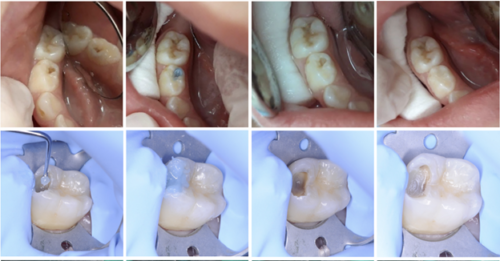

BRIX3000 được ra mắt vào năm 2012 và là một tác nhân cơ- hóa học dựa trên enzyme phân giải protein và papain, cho phép loại bỏ collagen theo cơ chế hóa học trong ngà răng. Lượng papain được sử dụng tương đương 3000U/mg ở nồng độ 10% sẽ mang lại cho gel một pH lý tưởng đảm bảo các enzyme có khả năng hoạt động tốt, thực hiện quá trình phân giải protein trên collagen của mô răng bị sâu. Enzyme papain chỉ tập trung vào lớp ngà nhiễm trùng.

Hình 1: Gel enzyme BRIX3000

Hình 2: Làm sạch lỗ sâu với BRIX3000, không sử dụng tay khoan